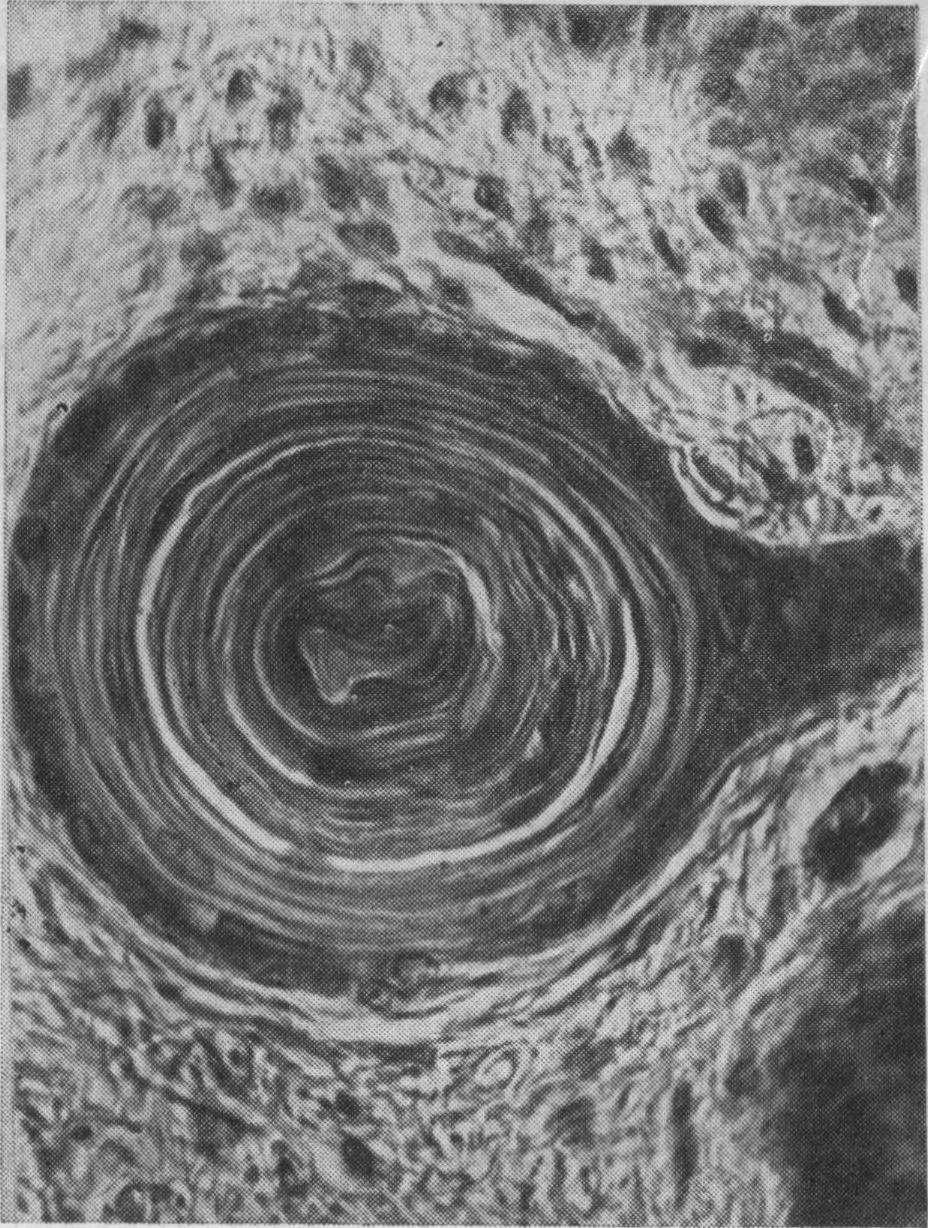

Рис. 12. Эпителий слизистой оболочки твердого неба. Окраска гематоксилин-эозином. X 200 (Шаймерденова Р. Ш.).

слизистой оболочки твердого неба, в том числе и в области срединного шва (рис. 12).

Важно отметить, что во всех зонах твердого неба, за исключением задней его трети в собственной пластинке, главным образом у плодов и новорожденных, выявляются весьма своеобразные крупные округлой формы структуры. Внутренние элементы их находятся в состоянии деструкции, прилегающие к ним клетки уплотняются, вытягиваются и располагаются концентрически. В клетках наружных слоев хорошо выражены ядра и цитоплазма. Описанные образования представляют собой не что иное, как эпителиальные жемчужины. Динамику их развития от ранних до более зрелых форм удается проследить уже у плодов и новорожденных (рис. 13). J. Schumacher (1927) также иногда находил их в различных местах твердого неба новорожденных.

Рис. 13. Сформированная эпителиальная жемчужина в эпителиальном тяже, погруженном в собственную пластинку слизистой оболочки альвеолярного отростка.

Новорожденный. Окраска гематоксилин-эозином. Х600 (Реброва М. А.).

н поздний типы жемчужин. Первый тип обнаруживается у эмбрионов длиной 3—5 см, жемчужины состоят из темных однородных клеток с шарообразным ядром, в котором четко видны глыбки хроматина. Затем периферические клетки сплющиваются и вытягиваются и образуют вокруг ороговевающих осевых клеток концентрические слои. Этот поздний тип эпителиальных жемчужин имеет более крупные размеры и выявляется у плодов длиной 25 см. Затем они постепенно уменьшаются, резорбируются и в дальнейшем не обнаруживаются. Чрезвычайно редко зрелые эпителиальные жемчужины встречаются в пожилом возрасте. По данным М. А, Ребровой, они (см. рис. 12) встречаются у детей, юношей и у лиц пожилого возраста, не пользовавшихся съемными пластинчатыми протезами.